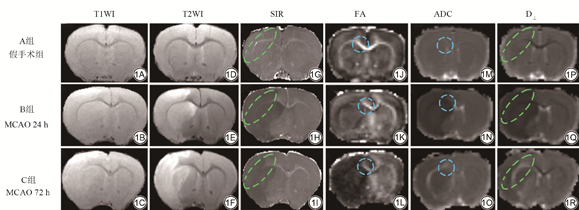

不同组别MCAO大鼠脑中具有代表性的T1WI、T2WI、SIR和DTI衍生的参数图像如图1所示,随着脑卒中的时间延长,各组别均可见外囊的显著信号变化,胼胝体变化不显著。

SD大鼠18只随机分成A、B、C三组,每组6只,A组进行大脑中动脉闭塞(middle cerebral artery occlusion, MCAO)假手术,暴露颈部血管而不结扎;B组为MCAO术后24 h组;C组为MCAO术后72 h组。相同条件下进行T1WI、T2WI、DTI扫描,后处理得到SIR、各向异性分数(fractional anisotropy, FA)、表观扩散系数(apparent diffusion coefficient, ADC)、垂直扩散张量(radial diffusivity, D⊥)图像,勾画胼胝体和外囊区域进行计算SIR值、FA值、ADC值和D⊥值,并进行三组间单因素方差分析。扫描结束后取材进行劳克坚牢蓝(luxol fast blue, LFB)-焦油紫病理染色,测量平均灰度值(mean grayscale value, MGSV)后进行3组间单因素方差分析。将差异具有统计学意义的影像学数据和病理学平均灰度值进行两两相关性分析。

18只SD大鼠随机分成A、B、C 3组,每组6只。A组进行MCAO假手术,B组为MCAO术后24 h组,C组为MCAO术后72 h组。MCAO手术方法如下:将SD大鼠用异氟烷麻醉后,经颈正中开口,暴露左侧颈总动脉(common carotid artery, CCA)和颈外动脉(external carotid artery, ECA)、颈内动脉(internal carotid artery, ICA),使用动脉夹夹闭CCA和ICA,结扎ECA,将24 mm线栓(深圳华阳实验室)沿着ECA、ICA到达大脑中动脉。假手术组大鼠只暴露左侧CCA、ICA、ECA,不做手术结扎。